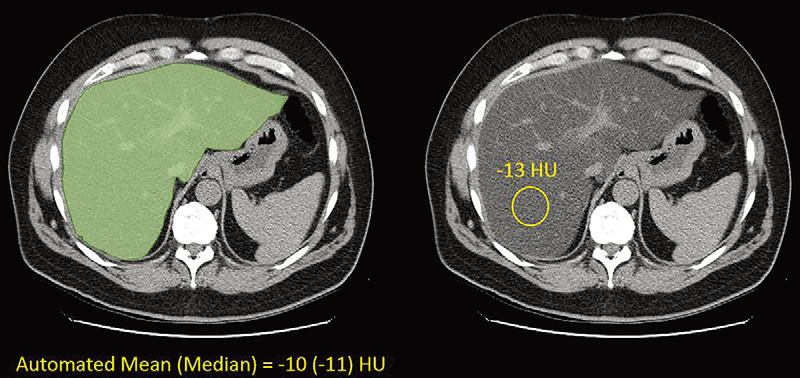

• 分析了基于体积的自动肝脏衰减,包括转换为CT脂肪级分,并在大量扫描中与手动测量进行比较。

• 自动和手动测量之间表现出极好的一致性,平均差为2.7 HU(中位数,3 HU)和r2的 0.92。在纵向随访的亚队列中,平均变化仅为-3 HU ±9,但43.3%(1861年中有806例)的患者在第一次和最后一次扫描之间改变了脂肪变性类别。